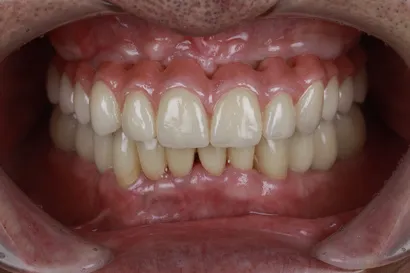

重度虫歯からの全顎インプラント治療

70代 男性

執刀医 Dr.大杉 治療内容 虫歯・歯周病が原因で噛み合わせが崩壊していたので、全顎的なインプラント治療を行い、口腔機能の回復を行いました。

上顎:ピンクポーセレンを用いたフルジルコニアインプラントブリッジ

下顎:奥歯=ジルコニアインプラントブリッジ、前歯=ジルコニアクラウン治療期間 1年6ヶ月 費用 上顎:420万 税抜

下顎:330万 税抜リスク セラミックのすり減りを防ぐために、ナイトガードを作成しています。毎晩使用することで、セラミックを長持ちさせることができます。 -